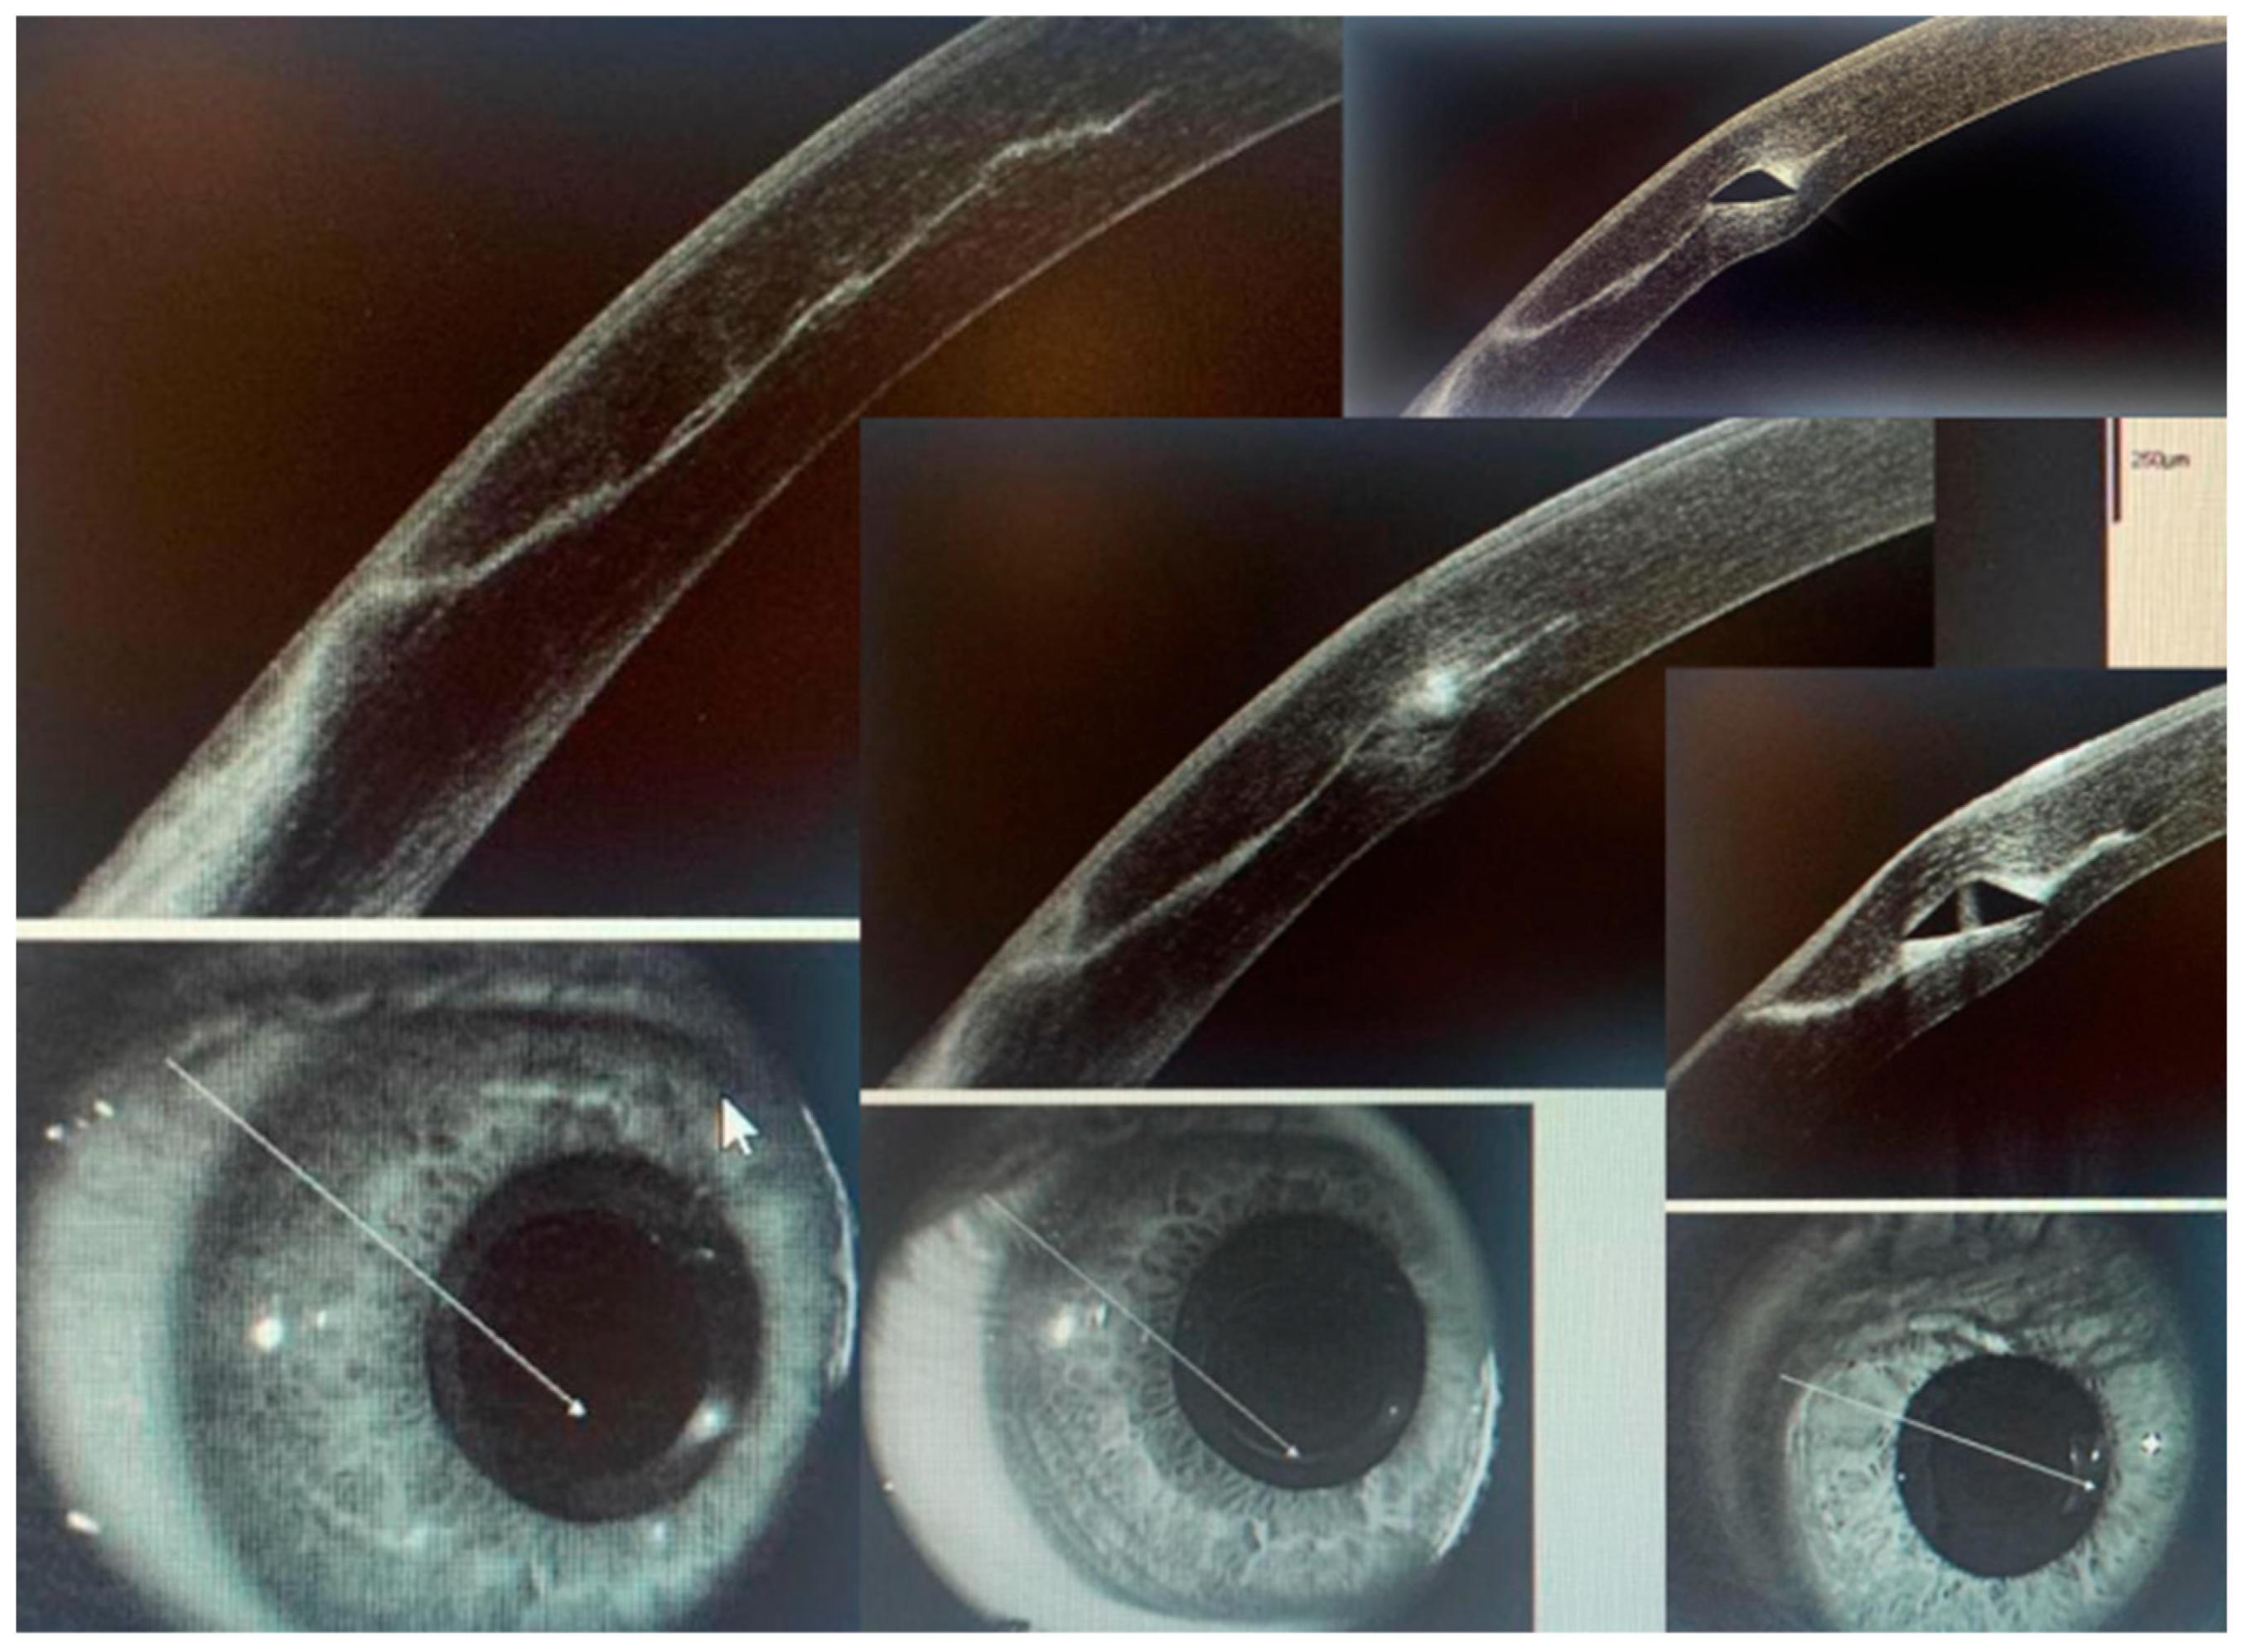

A sequence of corneal OCT images shows the perilimbal incision area and the tunnel area where the ICRS is implanted (Figure 6). A thin wound healing line can be seen progressing from the epithelium to the stromal tunnel one week after surgery. The edges of the wound are closed, as is the so-called “landing zone”. The OCT also allows us to observe the integrity of the corneal tunnel roof.

Figure 6.

Different corneal OCT images are presented to observe the wound healing zone, from the epithelium to the stromal tunnel where the ICRS is placed.